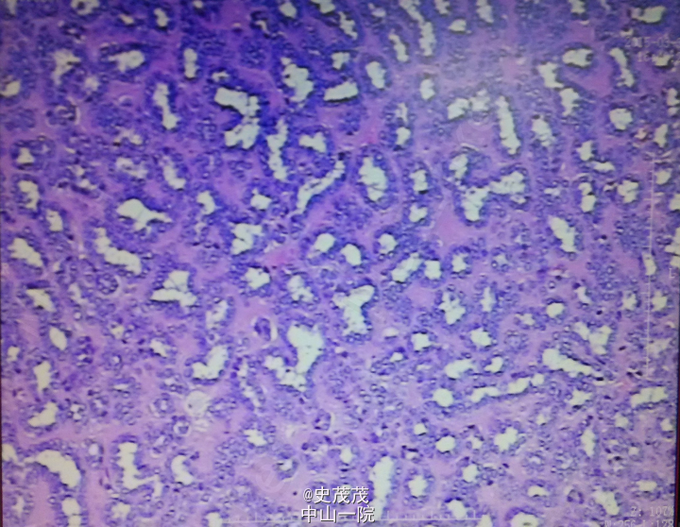

术后病理:右肾及肿瘤:17.5*12*7cm组织一块,切面见肿物14*12cm,大部分坏死,灰白,带输尿管8*0.3cm。镜检肿瘤带厚层纤维组织包膜,与肾实质界限清晰,肿瘤细胞呈小管状分布,细胞立方形,核圆形,大小形态较一致。IHC:CK+、Vim+、CD57+、EMA局灶+、CK7局灶+、CD10-、WT-1(-),Ki67约1%+。病变符合:(右肾)后肾腺瘤,输尿管切端未见肿瘤,肾门周围扪及淋巴结1枚,呈反应性增生,肾门脉管组织未见肿瘤。